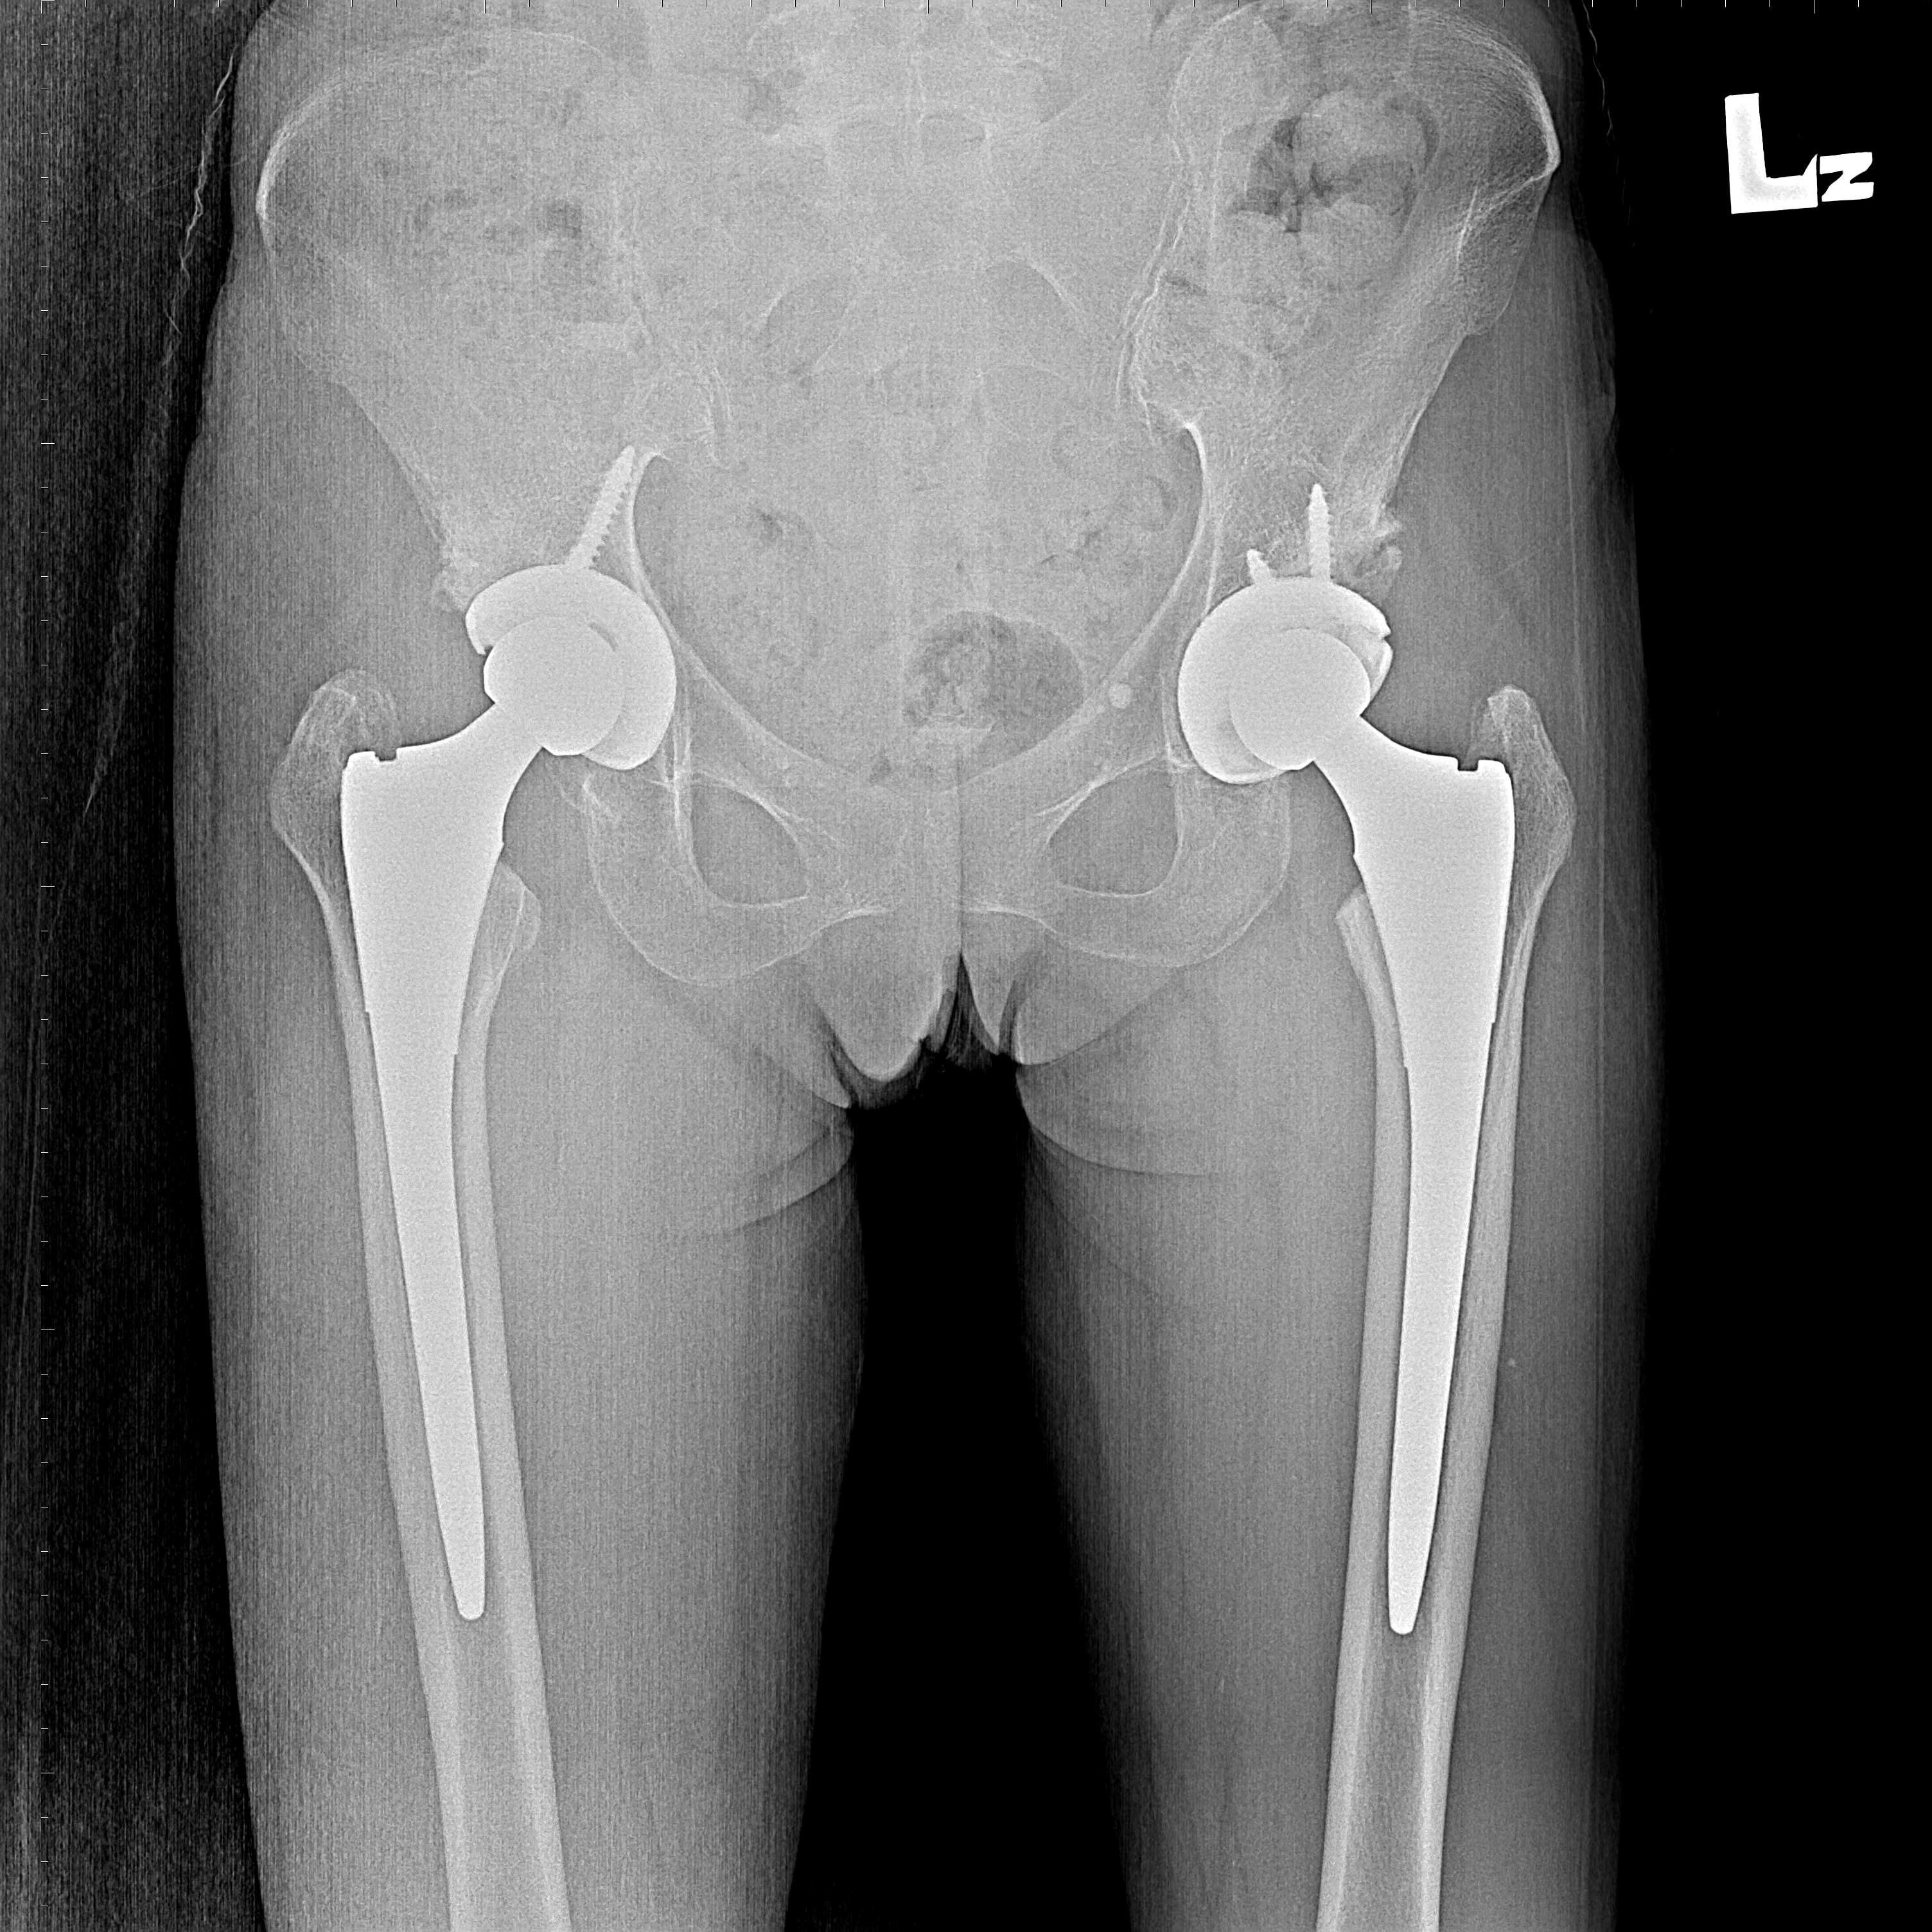

傳統髖關節置換 首頁 案例分享 髖關節手術 傳統髖關節置換 54歲蔡先生退化性關節炎 術前 術後 張女士 51歲 退化性關節炎(DDH先天發育不全 CROWE TYPE 2) 術前 術後 38歲林先生 退化性關節炎 術前 術後 72歲謝女士 退化性關節炎 術前 術後 71歲 謬女士 骨股頭壞死 術前 術後 50歲 郭先生骨股頭壞死 術前 術後 80歲 盧先生骨股頭壞死 術前 術後 林先生 37歲 術前 術後 邱女士 51歲 術前 術後 張女士 50歲 術前 術後